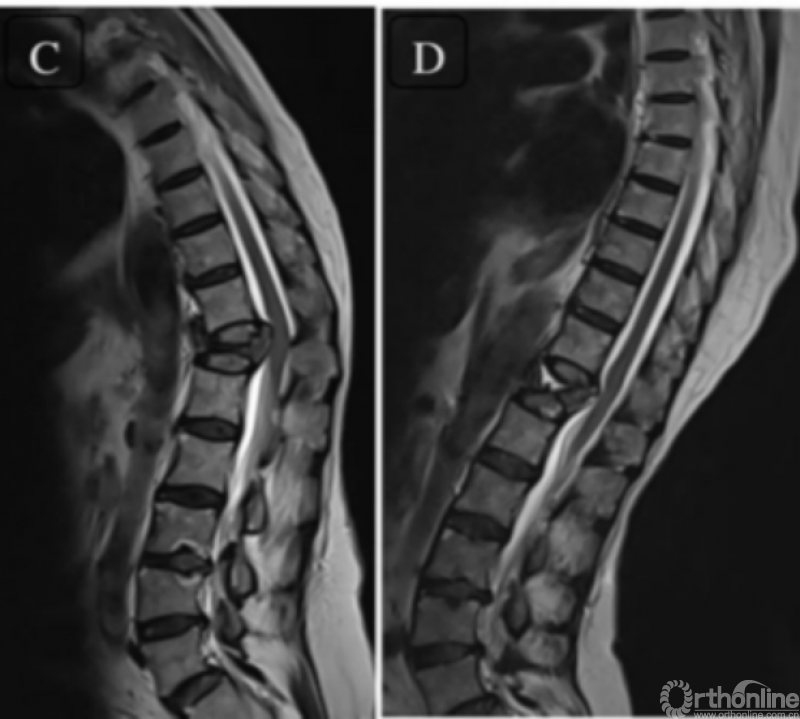

近年来,也有新的治疗技术和观点得以提出,值得探讨。Abhinandan等[7]在Global Spine Journal的文章指出,对于脊柱不稳定而非静态压迫导致的OVCF伴不全瘫患者,行体位复位固定融合手术而不进行椎管减压,可取得良好结果,作者认为OVCF伴不全瘫并非都需要直接减压,部分患者的不全瘫是由不稳定引起,动态MRI是进行准确诊断、制定手术策略的重要依据。

动态MRI检查方法

动态MRI判断脊髓压迫情况